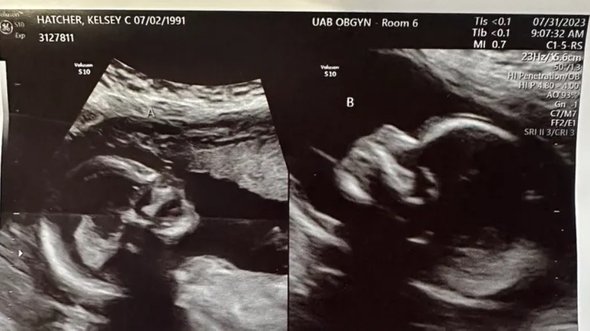

Гинеколог осмотрела ее на восьмой неделе беременности, сказала, что все в порядке и заверила, что плод развивается нормально. Тогда Келси сообщила врачу, что на самом деле у нее есть вторая матка, и попросила повнимательнее сделать УЗИ еще раз. Обе женщины страшно удивились, когда оказалось, что в каждой матке у Келси развивается по одному полноценному плоду.

Сейчас женщина проживает последний триместр своей необычной беременности. Врачи предложили ей немного «переносить» ее, чтобы дождаться естественных схваток, так как из уменьшенного размера маток и развивающиеся в них дети тоже будут несколько меньше известных стандартов. Сама Келси хотела бы родить естественным путем. Но врачи пока не могут выбрать ни одну из тактик, безопасную для матери и новорожденных. У них есть сразу несколько сценариев на этот счет. Например, схватки могут начаться в одной матке, и тогда одна девочка родится естественным путем, а вторые роды будут стимулировать. Также, возможно, придется просто сделать кесарево, чтобы обе девочки родились одновременно.